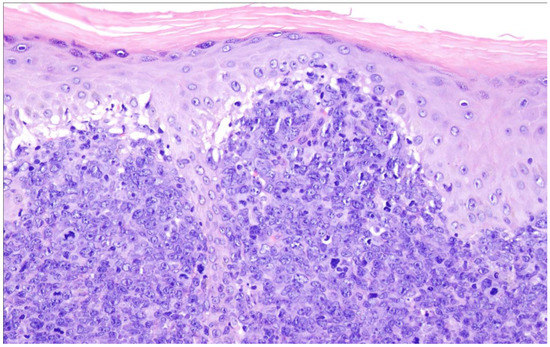

16. Primary Cutaneous Diffuse Large B-Cell Lymphoma, Leg Type

| Primary cutaneous diffuse large B-cell lymphoma, leg type |